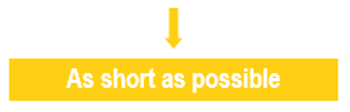

Lateral Resolution

As we mentioned previously, lateral resolution means the resolution of objects located side by side (perpendicular to the axis of the ultrasonic beam). The lateral resolution is directly related to the width of the ultrasound beam, which is inversely related to the ultrasonic frequency. It is the ability to distinguish between two separate objects that are close to each other and are in a direction perpendicular to the beam axis.

A high-frequency transducer emits a wave with short wavelength and reduced width of the ultrasound beam. The lateral resolution is weak when the 2 structures, side by side, are located in the same width of the beam. Since the return echoes overlap in this case, the two structures will appear as one in the corresponding image.

It is therefore important to choose high-frequency transducers, in order to keep the beam width as narrow as possible and achieve the best possible lateral resolution. However, attenuation also increases with frequency, so a compromise must be found between resolution and mitigation.

The beam width can be further reduced by adjusting the focal area. It is, therefore, useful to position the target structure in the focal zone to obtain the best possible lateral resolution. The beam diverges increasing its width while propagating in depth. It is possible to focus the ultrasound beam to obtain a narrow beam at the focal length, and thus improve the lateral resolution. Focusing can be accomplished either mechanically, or electronically via a multi-element array.